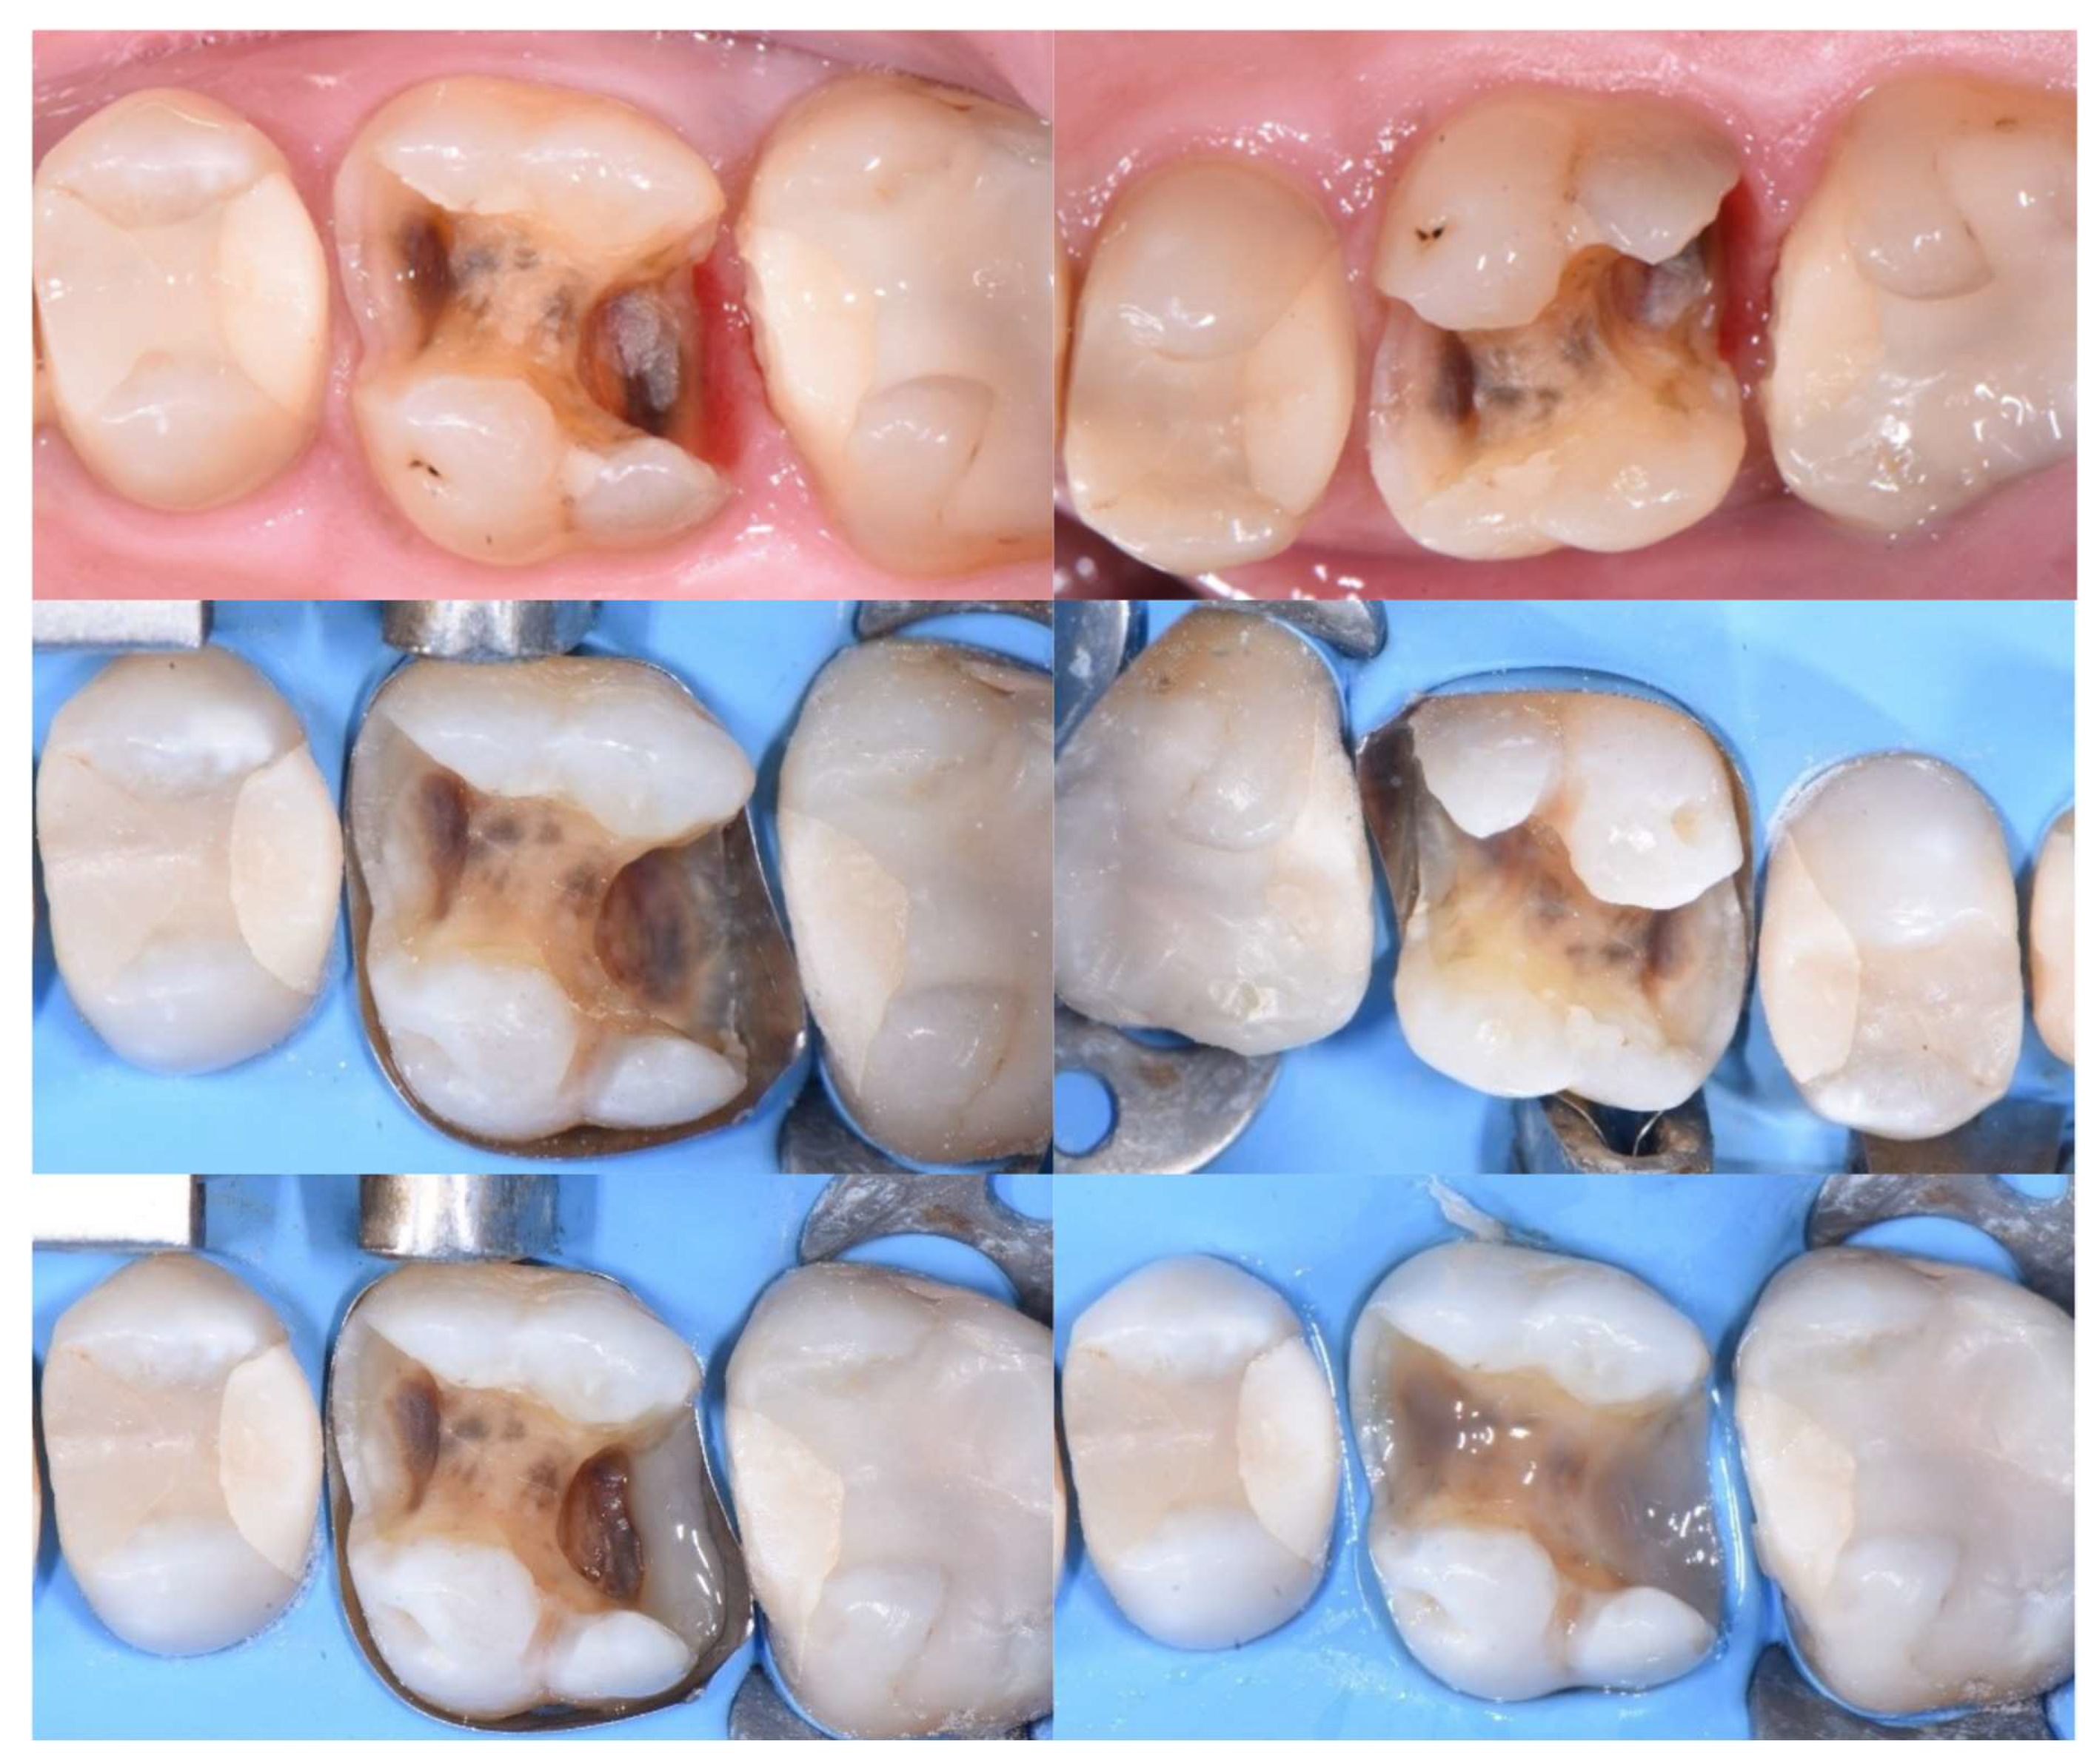

3.4. Microleakage & Marginal Adaptation

| Jawaed et al [32], 2016 | In vitro study | Total etch | Specimens were sealed with acid-resistant varnish, leaving a 1 mm margin around the cervical area, and immersed in 2% buffered methylene blue solution for 24 hours. Microleakage was evaluated under a stereomicroscope, scored (0–4), and measured in millimeters. | The "snowplow" technique ensures lower microleakage in DME situations, because it reduces the thickness of the flowable resin at the base, which—due to its lower filler content—exhibits greater polymerization shrinkage. |